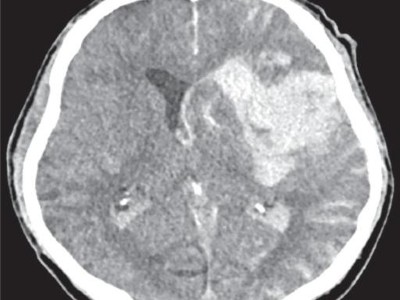

Ein Abszess auf Abwegen

Bei einer Krebspatientin wird ein verdächtiger mediastinaler Lymphknoten bronchoskopisch biopsiert. Kurz darauf entwickeln sich erst ein Lymphknotenabszess, dann eine Blutstrominfektion – und weitere vier Wochen später schließlich multiple suspekte Läsionen im Gehirn. Der Blick in das Herz der 69-Jährigen zeigt, wie es dazu kommen konnte.

Magnetresonanztomographie/© Svitlana / Stock.adobe.com (Symbolbild mit Fotomodell), Schaumiges Bronchialsekret bei akutem Lungenödem/© Eichner M. doi.org/10.1007/s00063-025-01258-9 unter CC-BY 4.0, Intrazerebrale Blutung nach mechanischer Thrombektomie/© Mohamad J / all rights reserved Springer Medizin Verlag GmbH, Intrakranielle Abszesse/© Seidl H et al. doi.org/10.1007/s00108-025-01863-y unter CC-BY 4.0, Bildtitel/© Klaus Eppele / stock.adobe.com (Symbolbild mit Fotomodell), Seniorin liegt reglos auf Boden/© Racle Fotodesign / stock.adobe.com (Symbolbild mit Fotomodell), Tumor im linken Kleinhirnbrückenwinkel und inneren Gehörgang (linkes Bild) und Tumor am Foramen jugulare (rechtes Bild)/© Springer Medizin, Eine Frau im MRT/© Maksym Povozniuk / stock.adobe.com (Symbolbild mit Fotomodellen), Passantin hilf Frau, die bewusstlos am Boden liegt/© M.Dörr & M.Frommherz / stock.adobe.com (Symbolbild mit Fotomodellen), CT-Aufnahme bei intrakranieller Hämorrhagie/© stockdevil / Fotolia, CT und MRT bei Schädel-Hirn-Trauma/© Springer Medizin Verlag GmbH, Junger Mann liegt auf CT-Liege/© LStockStudio / stock.adobe.com (Symbolbild mit Fotomodell), Lesion in the right-sided medial occipitotemporal gyrus/© Springer-Verlag GmbH, Frau bei Strahlentherapie/© (M) Mark Kostich / Stock.adobe.com (Symbolbild mit Fotomodellen), Search Icon, CT-Pulmonalisangiographie/© Das M et al. doi.org/10.1007/s00117-016-0100-3 unter CC-BY 4.0, Kanüle für Katheterbehandlung/© romaset / stock.adobe.com, Alter Mann in Sprechstunde mit junger Ärztin/© lordn / Stock.adobe.com (Symbolbild mit Fotomodellen)